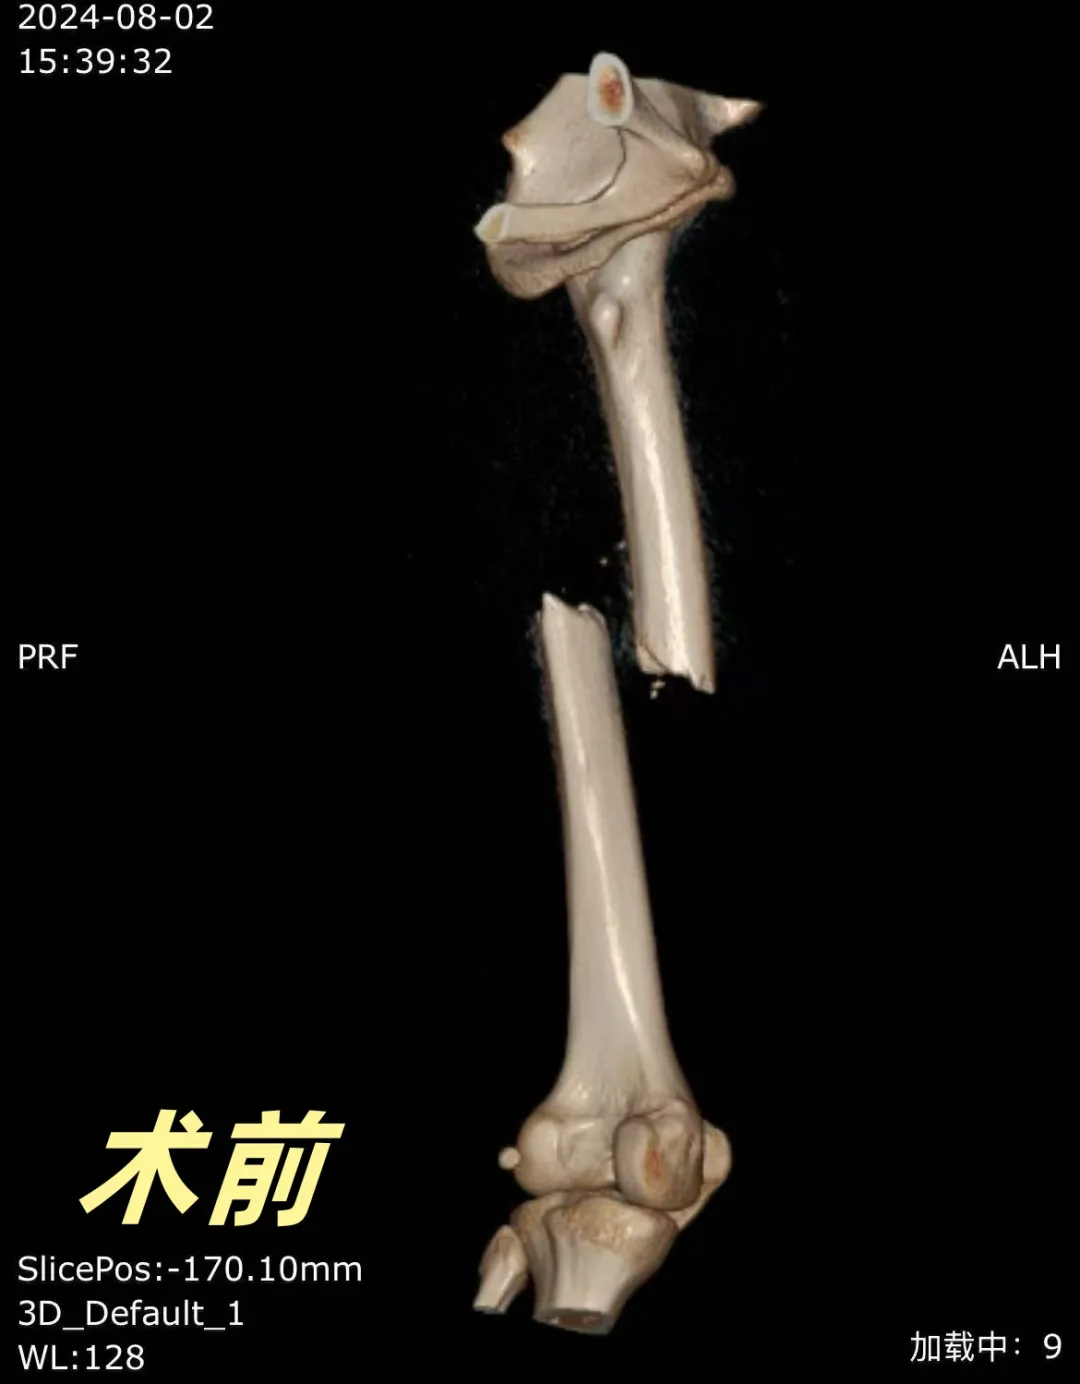

案例1

前不久“小明同学”骑电动车不慎摔伤左大腿,到威海卫人民医院关节外科门诊检查诊断为“左股骨中段骨折”,并予以初步固定,缓解患者疼痛。经过详细的检查和评估,专家团队决定为小明同学实施股骨髓内钉手术。手术由毕前航主任亲自主刀,凭借精湛的技术、丰富的髓内钉固定经验,团队默契配合精准地将髓内钉植入骨髓腔中,对骨折部位进行内固定。整个手术过程仅耗时一个多小时,出血量少,创伤小。

术后,关节外科制定了个性化的康复计划,包括物理治疗、功能锻炼和心理疏导等。小明同学在关节外科医护人员的精心护理下,骨折部位愈合良好,功能逐渐恢复,回到了正常的生活和学业轨道。